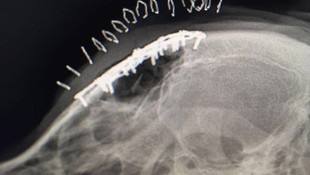

Barınakta darbedilen köpek, İÜ'de tedavi edildi